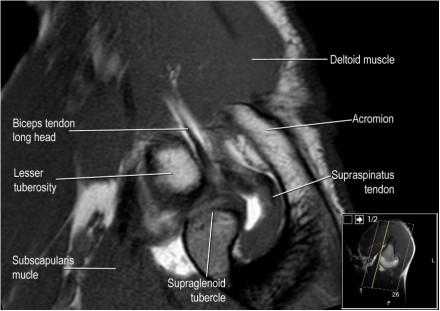

Нормальная сагиттальная анатомия и контрольный список

- обратите внимание на мышцы манжеты вращателей и поищите их атрофию

- обратите внимание на среднюю плече-лопаточную связку, которая имеет косое направление в полости сустава, и изучите отношение к сухожилию подлопаточной мышцы

- изучите место прикрепления длинной головки двуглавой мышцы плеча к суставной губе (biceps anchor)

- обратите внимание на форму акромиона

- поищите импинджмент за счет акромиально ключичного сустава. Обратите внимание на интервал между мажетой вращателей и клювовидно-плечевой связкой (coracohumeral ligament).